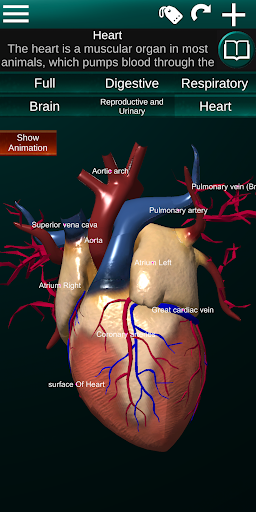

* Hart, dat de atria, ventrikels, aorta en een animatie van dit orgel omvat.

* Gemakkelijk te openen en te navigeren (zoom, 3D-rotatie).

* Verberg of toon informatie.

* Beschrijvingen van elk orgel.